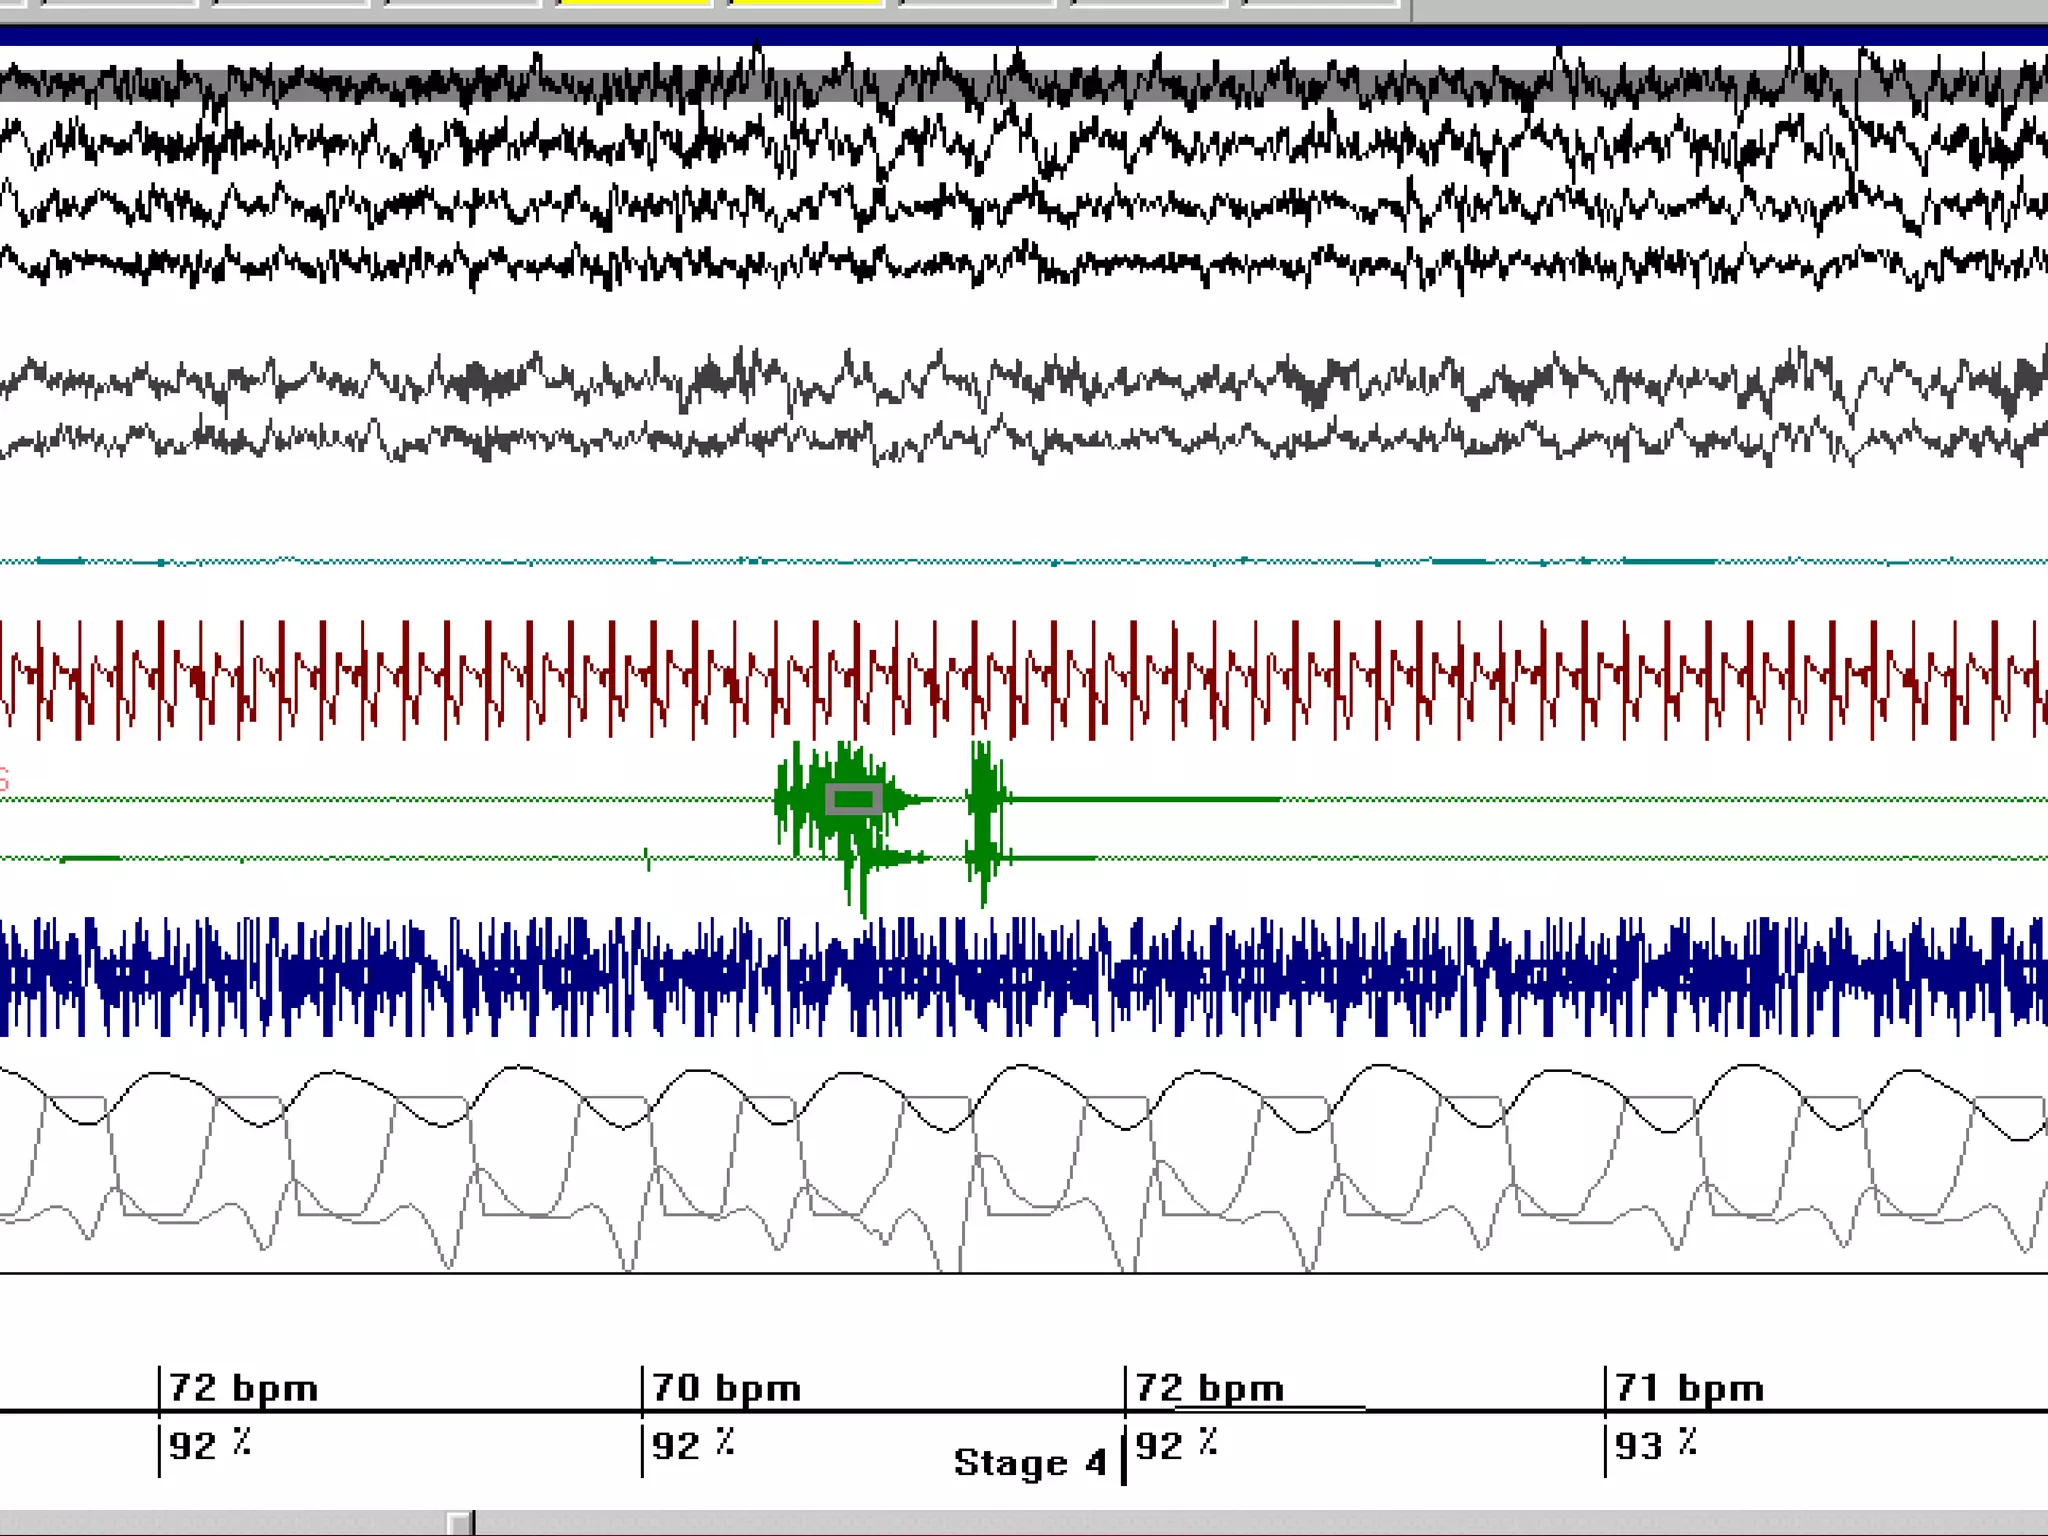

Polysomnography

Polysomnography is a simultaneous

recording of multiple physiologic

parameters related to sleep and wakefulness

– EEG

– EOG

– EMG

Parameters monitored:

1-Four (EEG) channels

2-Two  (EOG) channels

3-One (EMG) channel

4-Airflow( nasal and

oral) for the detection

of apnea

5-Sound recordings to

measure snoring

6-ECG

7-Pulse oximetry

8-Respiratory effort (Thoracic

and abdominal belts)

9- Tibialis anterior EMG

10-Detector of the body

position

11-Esophageal manometry

Videomonitored PSG

Neurologic monitoring Techniques

• Extended EEG ( 12-36) channel

• Repeated studies ,video monitored

DD:

• Nocturnal seizures

• Parasomnias

• REM behavioral disorders

Neurologic monitoring Techniques •Extended EEG ( 12-36) channel • Repeated studies ,video monitored DD: • Nocturnal seizures • Parasomnias • REM behavioral disorders